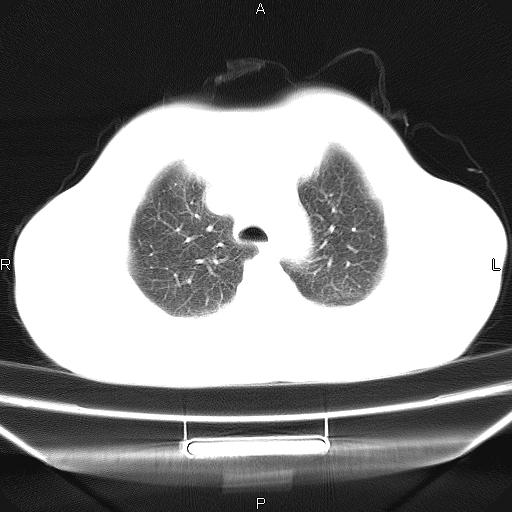

患者,男,40岁。间断发热,咳嗽二十余日。体温最高达38.9° 在当地诊所抗炎治疗三天后体温降至正常,患者自行停药。今又发热。胸片示,左下肺阴影。

左下肺片状高密度影,境界模糊,密度不均,考虑感染性病变可能性大,建议抗炎治疗后复查。左肺门增大,不除外占位性病变,必要时支气管镜检。